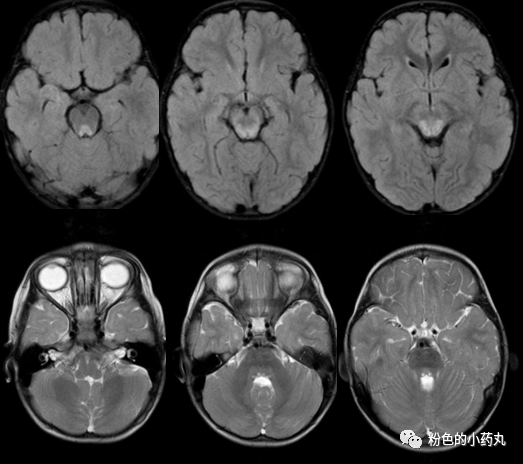

因遗传特征不同MRI通常呈异质性。一般来说,病灶分布对称。可分为三型: 基底节型、脑干型及白质型。

T2/FLAIR高信号,累及基底节中以壳核最多见,累及丘脑中以背侧丘脑内侧近第三脑室最多见。文献报道,双侧对称的壳核受累是必备的特征,尾状核、苍白球及丘脑可同时受累,但绝不会在壳核不受累的情况下单独出现。脑白质、皮层及小脑受累少见,病变范围较广可累及胼胝体和内囊。

T1常表现为低信号,但可见部分高信号,有一定强化。

图 病例4